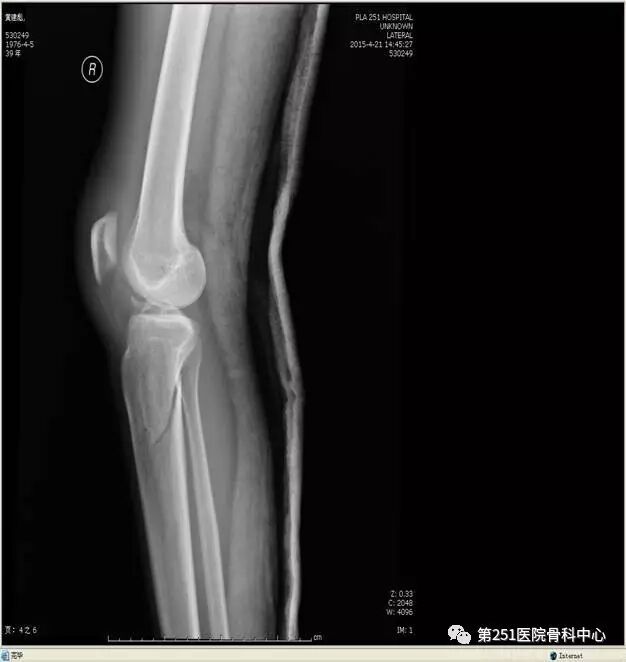

病例4:女性,车祸伤,同侧股骨、股骨颈合并胫腓骨骨折。

![]()